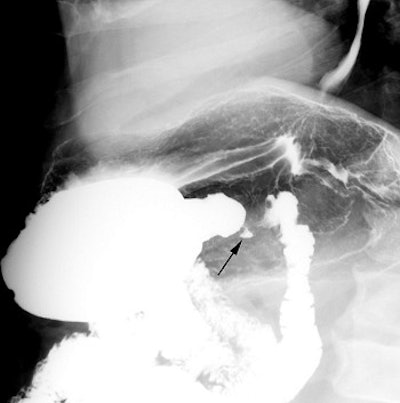

Above, an example of a pyloric channel ulcer (black arrow). Below, a spot compression view. Ulcers are often associated with NSAID usage.